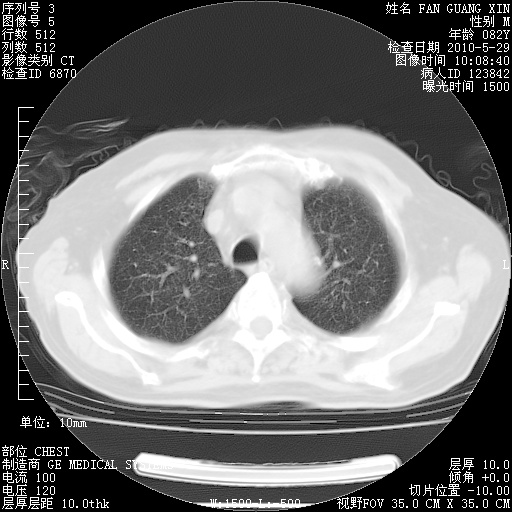

再治疗10天后的肺部CT 纵膈窗

阅读此次胸部CT,肺间质渗出性改变较入院时有吸收。目前从体温、白细胞、中性分叶明显增高,肯定存在细菌感染(发生医院感染哦,若无消化道及泌尿系统等感染的依据,肺部感染可能大)。若你院头孢哌酮舒巴坦钠耐药率较高,同意你的方案,若48小时体温仍高,可考虑使用碳青霉稀类抗菌药物,同时可予超声雾化、注意滴数时加大液体量。白蛋白33.30g/L较低哦,需加强营养等支持治疗。